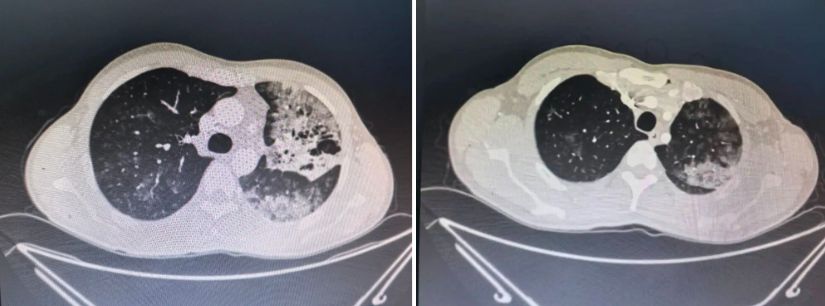

△患者康康(化名)2026年3月的CT影像

2025年10月,康康因咳嗽在当地医院被诊断为“肺炎”,抗生素、中药轮番上阵,症状却愈演愈烈。半年后CT显示:左肺病灶疯长,右肺新发多处渗出灶。

“康康在当地医院行气管镜检查,肺泡灌洗液脱落细胞学检查见高度异性细胞。当地医院推荐他到我们科来进一步明确诊断。”科室主任郭述良告诉记者。

尽管医生团队立即启动超声支气管镜引导下冷冻肺活检,最终组织病理锁定“肺腺癌”。但此时康康的癌细胞已弥漫双肺,手术刀已无法触及。

“患者罹患的是典型的‘肺炎型肺癌’。它披着‘肺炎’的外衣,一开始可能只有咳嗽、发热这些常见症状,等它显露出真容时,常常已进入晚期。”郭主任讲道。